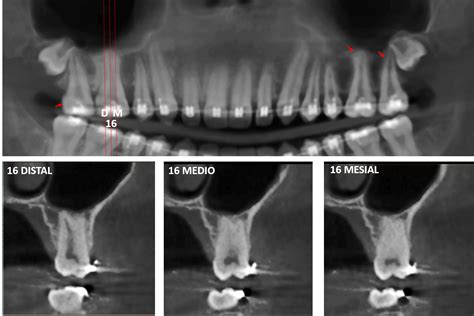

El diagnóstico del taurodontismo no siempre es evidente a través de una simple observación clínica, ya que los dientes afectados pueden parecer normales en el exterior. Por eso, el uso de radiografías dentales es esencial para identificar esta condición.

Si se sospecha de taurodontismo, se procederá a tomar radiografías para evaluar la estructura interna de los molares. Una vez confirmado el diagnóstico, se establecerá un plan de tratamiento personalizado. Dependiendo del estado de los dientes afectados, puede ser necesario realizar procedimientos de endodoncia compleja o restauraciones dentales.